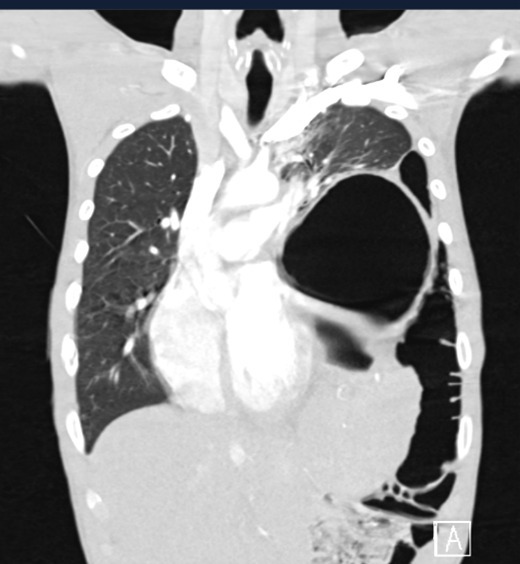

עם הגעתו של עוקל לרמב״ם בוצעה בדיקת CT דחופה, שהראתה ממצא משמעותי: "בצילומים נראה בקע סרעפתי גדול ודחיקה כמעט מלאה של הריאה השמאלית על ידי אברי הבטן שחדרו לחזה, עם חסימה של מוצא הקיבה – מה שהסביר את הכאבים וההקאות", מסביר ד"ר עמית כץ, מנהל מחלקת כירורגית חזה ברמב"ם שטיפל בעוקל, "הקרע הענק שראינו בסרעפת, נגרם למעשה כתוצאה מאותה תאונה שהמטופל היה מעורב בה כנער. כל השנים האלה, הוא הסתובב עם בקע שפוספס, הלך וגדל, עד להחמרה שהיתה כעת. זה לא מצב שכיח, אך בהחלט יכול לקרות במקרי טראומה מסוג זה. פציעות סרעפת בדרך כלל מתגלות בשלב מאוחר, משום שלא רואים אותן והן מתפתחות לאט לאט. לחץ הבטן גורם לזה שקרע קטן בסרעפת הולך וגדל עם הזמן".

בתמונה: צילום הדמיה של הפגיעה לפני הניתוח. צילום: הקריה הרפואית רמב"ם